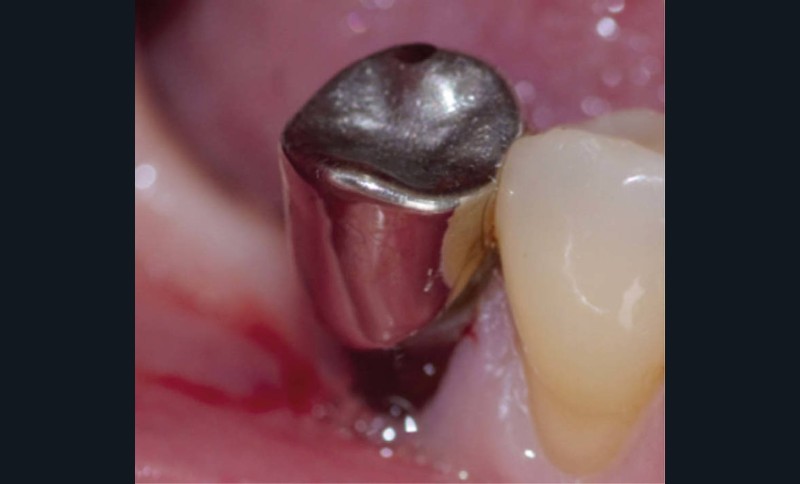

Une patiente de 53 ans, sans antécédent médico-chirurgical, consulte pour une gêne en lien avec une couronne métallique inadaptée sur la 45, réalisée une vingtaine d’années auparavant. L’examen clinique révèle un joint non étanche en vestibulaire associé à une lésion cervicale d’usure, nécessitant une réintervention et un retraitement endodontique. À la dépose de la couronne, la dent présente une reconstitution coronaire en amalgame ; aucune surface amélaire n’est présente et la prémolaire ne compte que deux parois avec une hauteur supérieure à 2 mm (fig. 1).